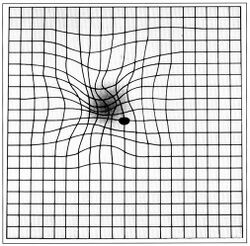

The Amsler grid test can be used to diagnose macular degeneration. For this test, patients are asked to look at a grid, and distortions or blank spots in the patient's central field of vision can be detected. A positive diagnosis of macular degeneration may account for a patient's micropsia.[6]